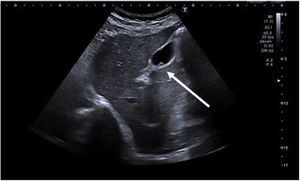

At our hospital, elective cholecystectomy surgery is indicated in patients with biliary symptoms and asymptomatic patients who present risk factors for malignancy, such as a polyp size greater than 10 mm, significant polyp growth observed on 2 consecutive imaging tests, and/or or concomitant cholelithiasis.1,7,8,10 The management algorithm for gallbladder polyps at our hospital is shown in Fig. 4.

In patients who do not meet the criteria for surgery, follow-up is carried out with ultrasound scans every 6 months during the first year, annually from the first to fifth years, and biannually thereafter, following the recommendations of most authors.1,7,10